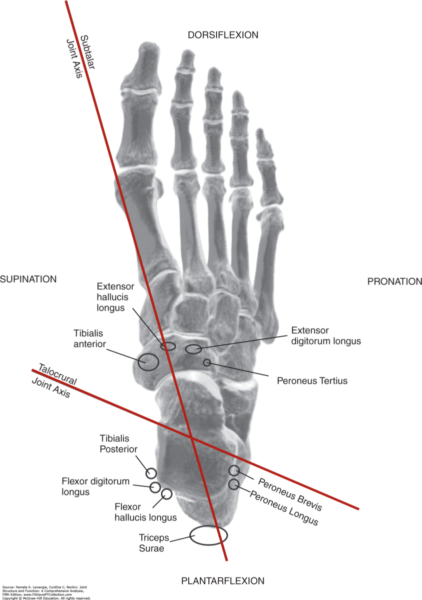

Peroneals: Both peroneus longus (inserting at the base of the first metatarsal and medial cuneiform) and peroneus brevis (inserting at the base of the fifth metatarsal) run posterior to the lateral malleolus. Their oblique tendon pathways create a mechanical advantage; the angular deviation means they can generate strong eversion moments with relatively modest muscle force.

The peroneals’ pathway gives them leverage over the subtalar joint axis. This angular deviation allows them to produce eversion efficiently, acting as both stabilisers and antagonists to the posterior tibial tendon.